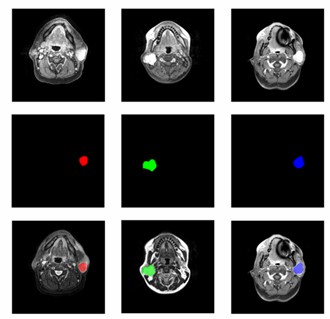

MRI image of parotid tissue. (Chang, 2021)

2. Chang, Yi-Ju et al. "Classification of parotid gland tumors by using multimodal MRI and deep learning." NMR in biomedicine. 34,1 (2021): e4408. Distributed under Open Access license CC BY 4.0, without modification.